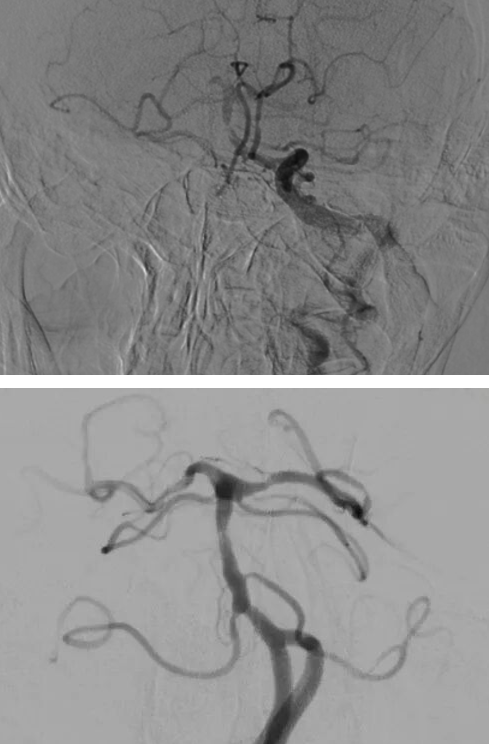

经过充分沟通,神经介入团队决定为他施行“基底动脉球囊扩张成形术”——一种微创介入手术。手术顺利完成后,复查显示血管血流保持稳定,未植入支架。

(▲基底动脉球囊扩张成形术前与术后对比)

术后,汤先生头晕、行走不稳明显好转,肢体乏力未再发作,目前已康复良好。